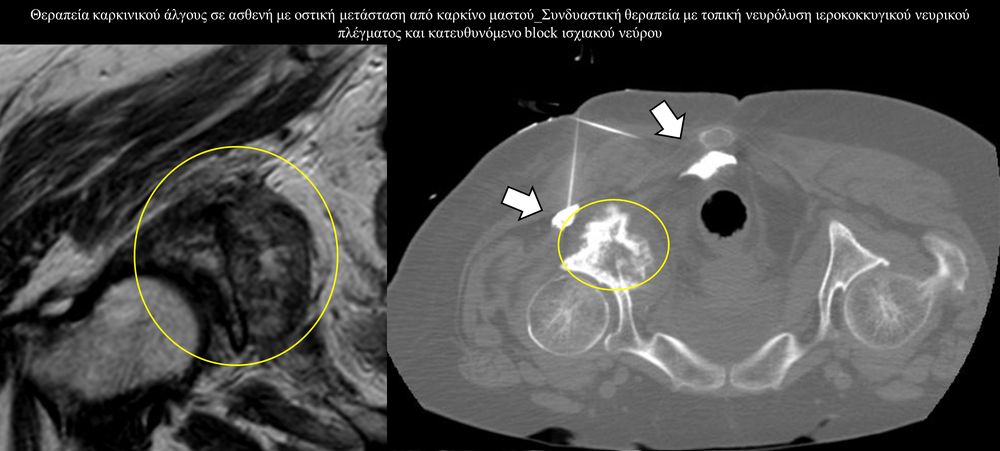

Η αντιμετώπιση του καρκινικού πόνου, εκτός από την κλασική συντηρητική φαρμακευτική θεραπεία, όταν ο πόνος επιμένει ή όταν οι παρενέργειες των φαρμακευτικών μεθόδων εξαντλούν τον ασθενή, περιλαμβάνει ελάχιστα παρεμβατικές τεχνικές με τις οποίες επιτυγχάνεται διακοπή ή καταστροφή της νευρικής οδού μεταβίβασης του πόνου. Η επεμβατική ακτινολογία διαθέτει μια πληθώρα θεραπευτικών τεχνικών που σκοπό έχουν να προσφέρουν ποιοτική βελτίωση της ζωής και των σχέσεων, τόσο των ογκολογικών ασθενών, όσο και των οικογενειών τους.